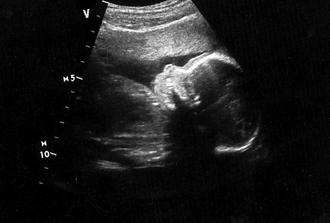

Majdulka (oficiálně Markéta) se narodila 21. 10. 2008 v 19:52 a měřila 50 cm a vážila 3530 g.